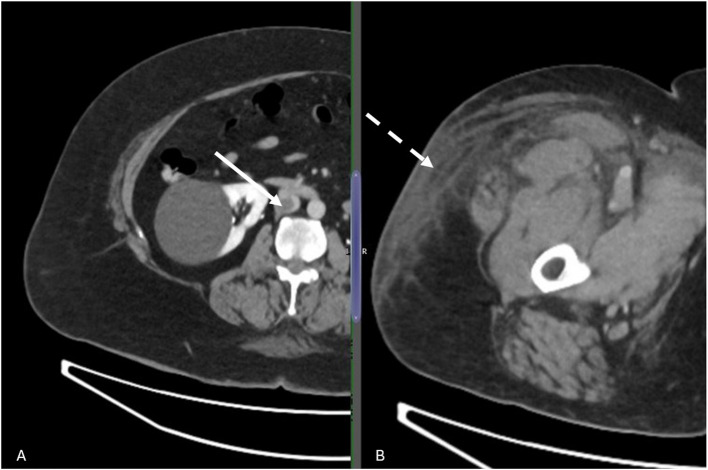

Abstract Image